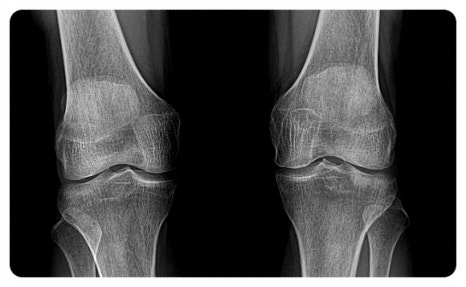

Q. 연골이 갈린다는 말, 정말 맞는 이야기인가요?

조금 과장되게 들릴 수는 있지만, 비유적으로는 맞는 표현입니다.

연골은 관절에 가해지는 충격을 완화해 주는 쿠션 같은 조직입니다.

그런데 발의 정렬이 틀어져 하중이 한쪽으로만 반복해서 실리게 되면, 특정 부위가 계속 압박을 받게 됩니다.

이 과정에서 연골은 서서히 손상될 수밖에 없습니다.

진료를 하다 보면 “특별히 다친 기억은 없는데 계속 아프다”고 말씀하시는 분들을 종종 만나게 됩니다.

실제로 검사를 해보면 무릎 연골이 한쪽만 얇아져 있는 경우도 적지 않은데요.

이는 갑자기 생긴 문제가 아니라, 잘못된 보행 습관이 오랜 시간 누적된 결과라고 볼 수 있습니다.